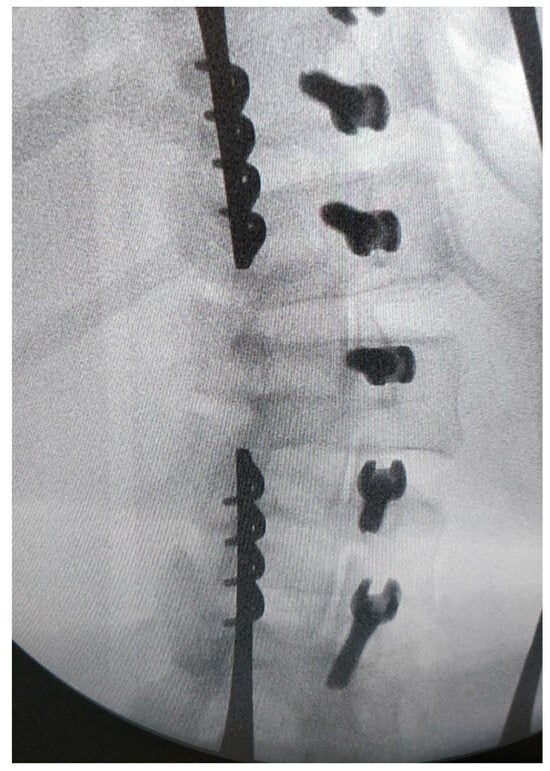

2.2. Surgical Technique